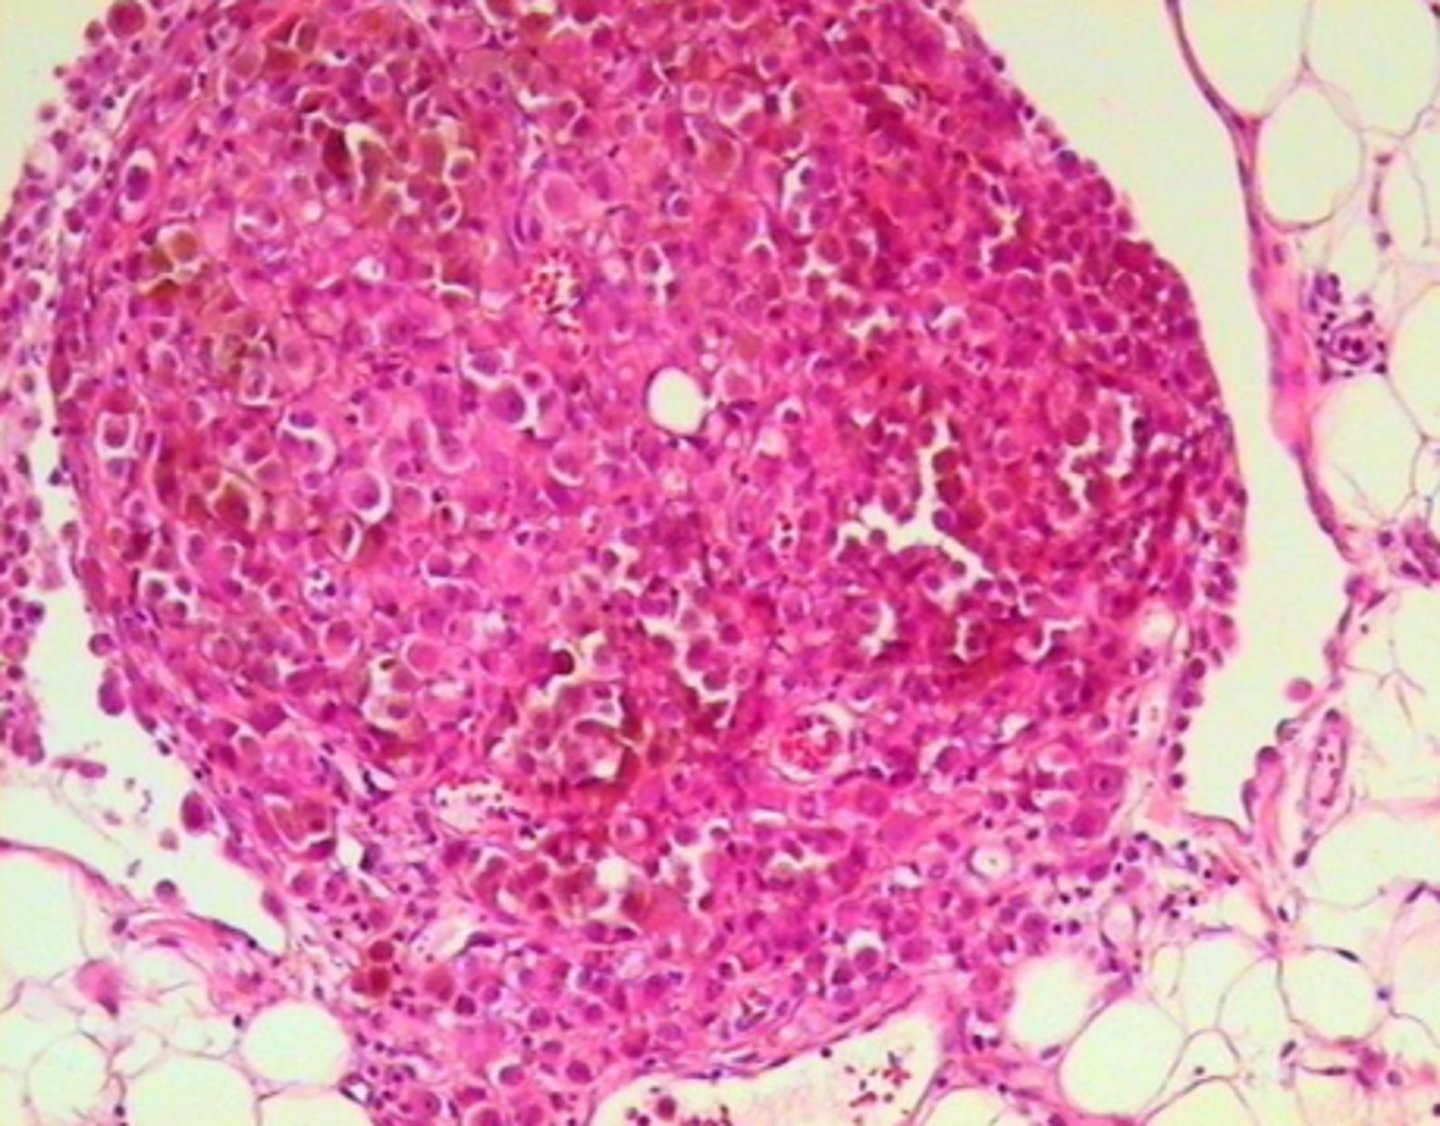

Melanomas metastāze taukaudos (omentā)

8

New cards